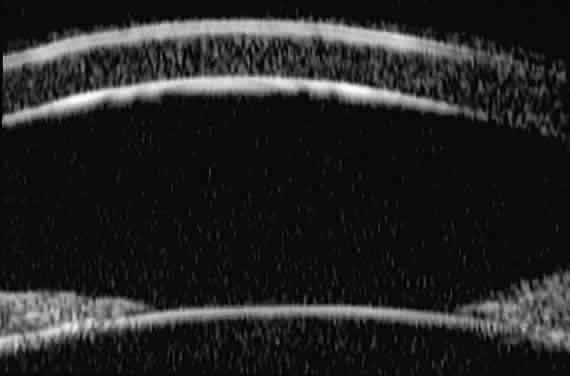

of the angle. In open-angle glaucoma, UBM can be used to measure the anterior chamber

angle in degrees, to assess the configuration of the peripheral iris, and

to evaluate the trabecular meshwork (Fig. 9).2,4 The angle configuration can be graded and compared with gonioscopic findings. In

is hazy or opaque.  Fig. 9. Angle configuration in eyes with open-angle glaucoma. A. Wide open angle with flat iris plane (D40r configuration by Spaeth gonioscopic

grading system). B. Moderately wide angle with anteriorly bowed iris plane (C30r by Spaeth

gonioscopic grading system). Fig. 9. Angle configuration in eyes with open-angle glaucoma. A. Wide open angle with flat iris plane (D40r configuration by Spaeth gonioscopic

grading system). B. Moderately wide angle with anteriorly bowed iris plane (C30r by Spaeth

gonioscopic grading system).